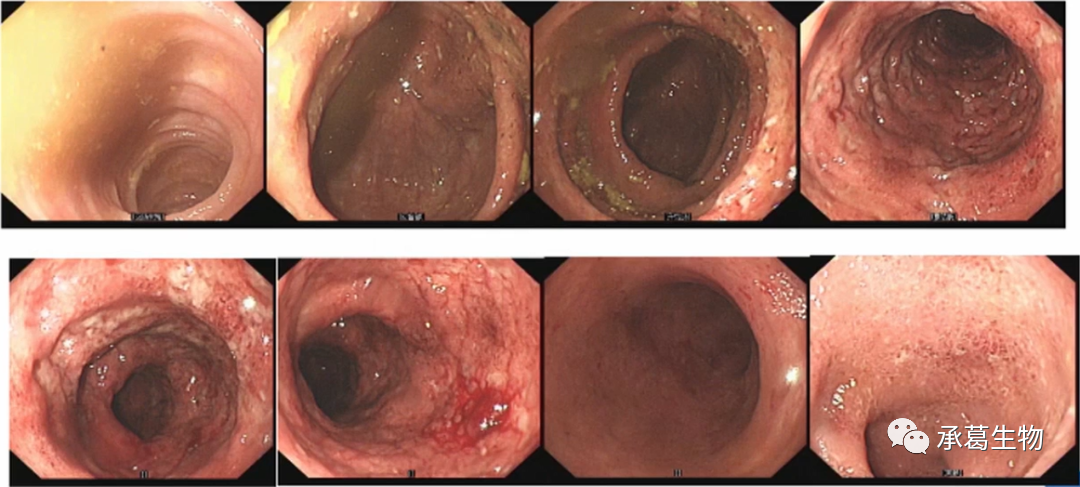

2022年8月再次無明顯誘因腹瀉加重至10余次/日,粘液膿血便,消瘦明顯,再次入院。查體示貧血貌、慢性病容、營養(yǎng)差、瞼結(jié)膜蒼白、雙下肢重度凹陷性水腫。血常規(guī)WBC、HGB均異常,CHE 301U/L,ALB 17.3g/l,重度貧血指征。糞常規(guī)示W(wǎng)BC+,RBC+++,隱血陽性,炎性指標(biāo)異常,巨細(xì)胞病毒及艱難梭菌均陽性。雙肺多發(fā)炎癥滲出,較前加重,左肺上葉結(jié)節(jié)新發(fā),雙側(cè)胸腔積液,升-橫-降結(jié)腸管壁較前增厚,滲出增多,腹腔腸管擴(kuò)張。

予營養(yǎng)支持、抗菌抗病毒、美沙拉嗪、益生菌等治療,腹瀉次數(shù)由10余次減少至7-8次/日,炎性指標(biāo)仍異常,艱難梭菌、巨細(xì)胞病毒及單純胞疹病毒I型均呈陽性。繼續(xù)加強(qiáng)營養(yǎng)及抗菌抗病毒治療。大便次數(shù)較前稍減少,5-6次/日,稀水便或稀糊便,營養(yǎng)狀況改善,艱難梭菌仍陽性,巨細(xì)胞病毒轉(zhuǎn)陰。2022年9月復(fù)查腸鏡示全結(jié)腸彌漫水腫覆灰苔及糞便,結(jié)腸袋消失,大片潰瘍,結(jié)節(jié)樣增生??紤]加強(qiáng)營養(yǎng)、生物制劑轉(zhuǎn)換、菌群移植、抗感染等治療。

(2022年9月腸鏡)